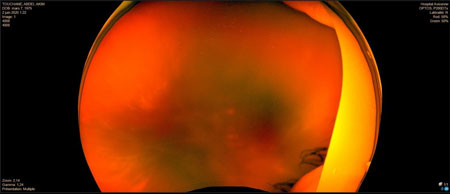

DR tractionnel préop

DR tractionnel post op

préop HIV + rétrohyaloïdienne

post op idem

HIV préop

HIV post op